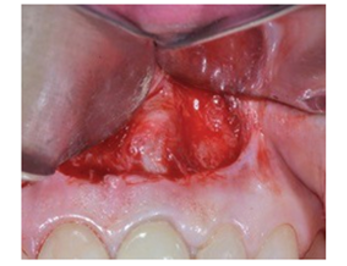

图3:Partch切口暴露根尖病变

图 4:根尖切除术和病变

消除